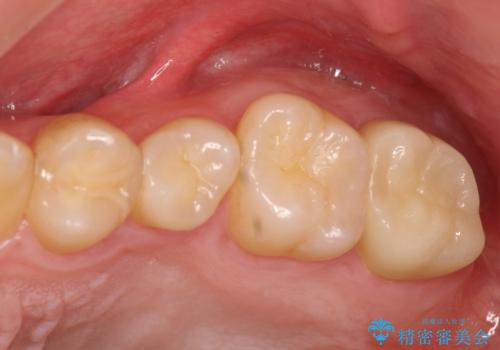

[フルジルコニアクラウン] 老朽化した銀歯を白く